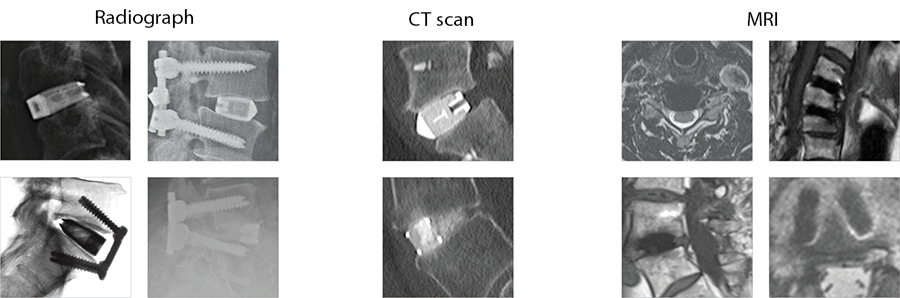

The implants' porous structure enables excellent visualization both intraoperatively and postoperatively on imaging modalities without interference (Fig 3).